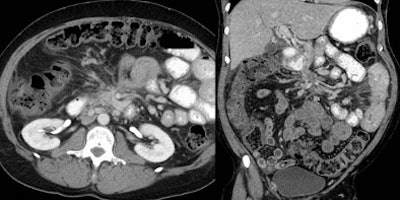

![]() |

| Sixteen-row MDCT scanner images of a patient with chronic pancreatitis presenting with abdominal pain. MPRs enabled the diagnosis of fibrosing enteritis, and its importance was rated 3. All images courtesy of Dr. Vassilios Raptopoulos. |